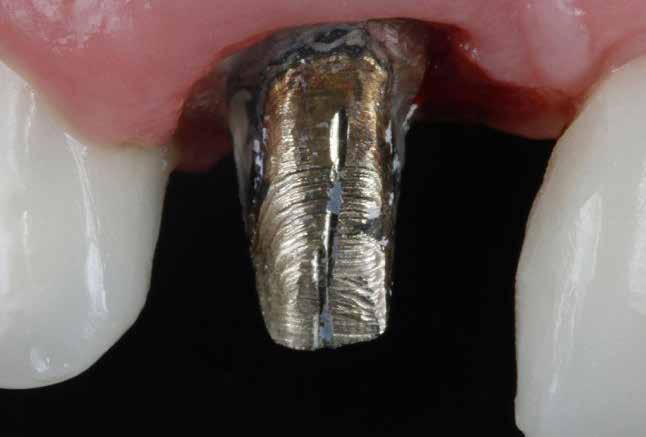

A mindennapi gyakorlatban gyakran találkozunk súlyos fogszuvasodással. A fogorvosnak mindig kihívást jelent a döntés, hogy kihúzzuk és implantátummal pótoljuk, vagy megmentjük a fogat, de kétséges a hosszú távú prognózis. Számos cikkből tudjuk, mint például Seltzer és Kim (Comparison of Long term survival of implant and endodontically treated teeth J Dent Res 93(1):19-26, 2014) cikke, hogy a fogak viszszanyerése jobb megoldás, különösen a fiatalabb betegeknél. A kirakós hiányzó kulcsa az általános fogorvos számára gyakran a maradó fogazat jó biomechanikai értékelése. Az endodontikusan kezelt fogak kudarcainak többsége valójában mechanikai hibákhoz, például repedéshez és töréshez kapcsolódik. A maradó fogszerkezet gondos biomechanikai értékelése, valamint a mechanikai teljesítményt javító technikákra való összpontosítás a legfontosabb a hosszú távú eredmény keresésében. A szerző praxisában a vertikális pre-

parálás és a minimális megközelítés kombinációja, valamint az ortodontikus extrúzió alkalmazása a restauratív fogászatban megváltoztatja a helyzetet, amint azt a következő eset is mutatja.

Az implantológia térhódítása után a restauratív/protetikai fogászatban a léc magasabbra került. A fogászati implantátumokkal való sikeresebb „versenyzéshez” a fogorvosoknak sokkal jobban kell összpontosítaniuk a fogak biomechanikai helyzetének értékelésére és javítására. A biomechanika mély megértése és a fogak teherbíró képességét javító technika alkalmazása a legfontosabb a hosszú távú siker érdekében.

Egy 35 éves kaukázusi férfi páciens az 1.4-es fog (felső első premoláris) törése miatt kereste fel rendelőnket, a törés ferde volt. A sérült fogak helyreállítása során az egyik legfontosabb lépés a megmaradt fogazat biomechanikai értékelése . Egy hiba ebben a fázisban káros a hosszú távú eredményre . A legtöbb repedést például a fogüregek helyreállító fogászathoz való helytelen előkészítése okozza. Ugyanígy a fennmaradó szerkezet helytelen értékelése idővel mechanikai okokból bekövetkező meghibásodáshoz vezethet.

2. ábra: Az okkluzális nézet a fogszerkezet mennyiségét mutatja, a röntgenfelvételen az 1.5. fogon II. osztályú szuvasodás is látható. Még ha lehetséges is ezeket az eseteket koronahosszabbítással kezelni, a végeredmény átlagosan nem kielégítő. A ferrule gyógyulása korlátozott, és olyan parodontális szövődményekkel is találkozunk, mint a fekete háromszögek, a szomszédos fogak gyökérkitettsége. A fogszabályozó extrúzió sokkal előnyösebb.

4. ábra: A fogszerkezet helyreállítása és a fogrestaurációs komplexum ellenálló képességének javítása érdekében ortodontikus extrúziót végeztek a szomszédos fogakra ragasztott drót és egy egyszerű rugalmas ligatúra segítségével.

5. ábra: Az extrudálás nyomon követése néhány hét múlva. Az extrúzió végén a lágyrészek kisebb mértékű újrakontúrozása történt. A szerző általában fibrectomia nélkül végzi az extrúziót, és az extrúzió végén a lágyrészek újrakontúrozását végzi.

6. ábra: A fog az extrúzió és a függőleges preparálás után. A függőleges preparáció a legjobb preparátum a fog szerkezetének megőrzése szempontjából, különösen akkor, ha minimálisan invazív megközelítéssel alkalmazzák. A szerző egy módosított vertikális technikát alkalmaz, amely nagyobb hangsúlyt fektet a pericervikális dentin fenntartására.

7. ábra: A bukkális szerkezet összehasonlítása extrudálás előtt/után . A maradék fogazati struktúra okklusális terhelése most sokkal kedvezőbb a hosszú távú eredmény szempontjából .

8. ábra: Ideiglenes eltávolítás. 9. ábra: Még a szájpadlásfalon is volt fogazati struktúra-gyarapodás. A szájpadlásfal mintegy 35%-a már szilárd fogazati struktúrán van. Ez a jobb biomechanika miatt sokkal jobb eredményt tesz lehetővé a későbbi restauráció számára.

10. ábra: A cirkónium-dioxid korona cementálása üveg-ionomer cementtel . Ezzel a megközelítéssel nyilvánvaló, hogy a ferrule menynyisége a szomszédos fogakra gyakorolt bármilyen komplikáció nélkül nyert. A parodontális apparátus valójában érintetlen. Nincsenek fekete háromszögek, nincs a szomszédos fogak gyökérkitettségének kockázata. Már a szülés napján megvan a papilla, amely kitölti az intraproximális tereket. A nyert ferrule mennyisége hatalmas. A bukkális falon könnyen felismerhetjük, hogy az egész fal már szilárd fogazati struktúrán van, a palatális falon pedig az ajánlott 1-1,5 mm-nél jóval több. A függőleges preparálással szintén könnyen meg tudjuk tartani a visszanyert fogszerkezet mennyiségét , különösen a pericervikális dentin területén, ami a legfontosabb a hosszú távú eredmény szempontjából.